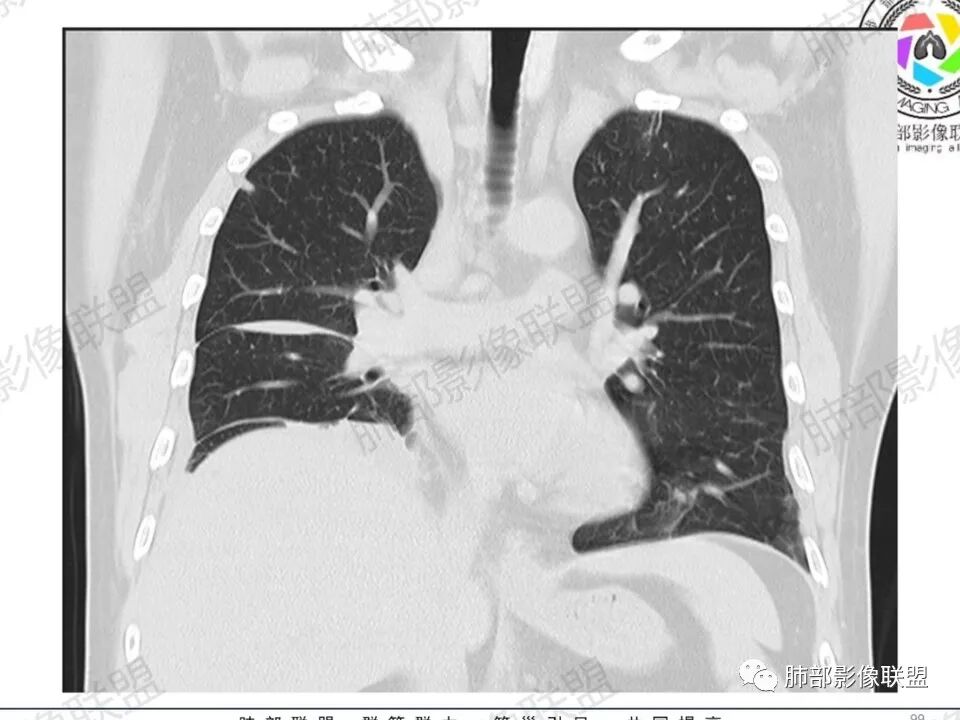

双肺多发结节,胸膜下为主,部分可见空洞。左肺上叶尖后段结节较大,分叶毛刺,周围可见长条索及小斑片影,内空洞比较光滑,内侧壁可见支气管通过。右肺下叶后基底段不张实变,后侧积液,右侧水平裂积液,右侧膈胸膜纵膈胸膜增厚积液,右侧侧胸膜肥厚,考虑1:一元金葡。2二元:金葡,左肺上叶结核。

中年男性,左手中指及胸壁疼痛伴发热来诊,影像见双肺多发结节,胸膜下分布为主,部分结节可见空洞,边缘模糊。左肺上叶尖后段结节较大。右肺下叶后基底段不张实变,右侧叶间裂及右侧胸腔积液,右侧侧胸膜肥厚。考虑金葡菌感染,血播SPE。

胸膜下为主多发结节,边缘光滑

伴随楔形影,支气管壁不增厚